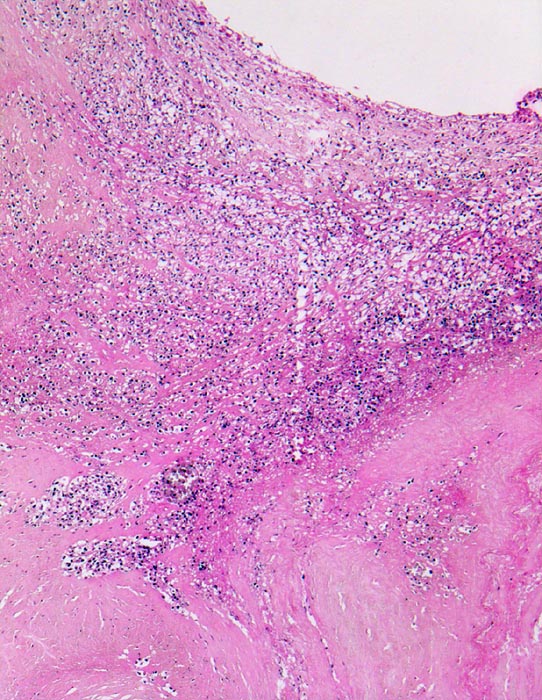

Morphologische Merkmale:

• Längsschnitt durch Aorta, Aortenklappe und linkes Ventrikelmyokard.

• Oben im Bild die Aorta mit kleinem Fibroatherom.

• Abszedierende Entzündung der aortalen Adventitia ausgehend von septikopyämischen Streuherden.

• Ulzerierte Aortenklappe(ulcerosa).

• Dem ulzerierten Klappengerüst aufgelagerte polypöse Vegetation aus Fibrin und Granulozyten durchsetzt von blauen Kokkenbakterienkolonien (polyposa).

• Ausgedehnte frische Koagulationsnekrose (unsichtbare Zellkerne, Infiltrate neutrophiler Granulozyten) des linken Ventrikelmyokards unterhalb der Klappe.

• Mehrere septikopyämische Streuherde (blaue Bakterienhaufen in intramyokardialen Blutgefässen umgeben von Mikroabszessen).

Histologisch findet sich bei ulzeropolypöser Endokarditis ein Fibrin-Thrombozytenthrombus, welcher von Bakterien durchsetzt ist (=Vegetation). Die Vegetation sitzt auf einem Klappendefekt an dessen Basis Granulationsgewebe einzusprossen beginnt, welches den Thrombus organisiert. Klappendefekte, Gefässeinsprossungen, verdickte Sehnenfäden (> 2848) oder Kommissurenverwachsungen (> 8389) der Taschenklappen weisen morphologisch auf eine abgeheilte Endokarditis hin.